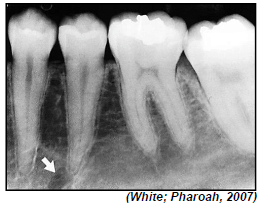

Equívocos durante o diagnóstico radiográfico podem levar a não indicação de tratamentos necessários, ou mesmo a procedimentos clínicos iatrogênicos. Analise a imagem abaixo.

Qual é a estrutura anatômica indicada pela seta na imagem anterior?